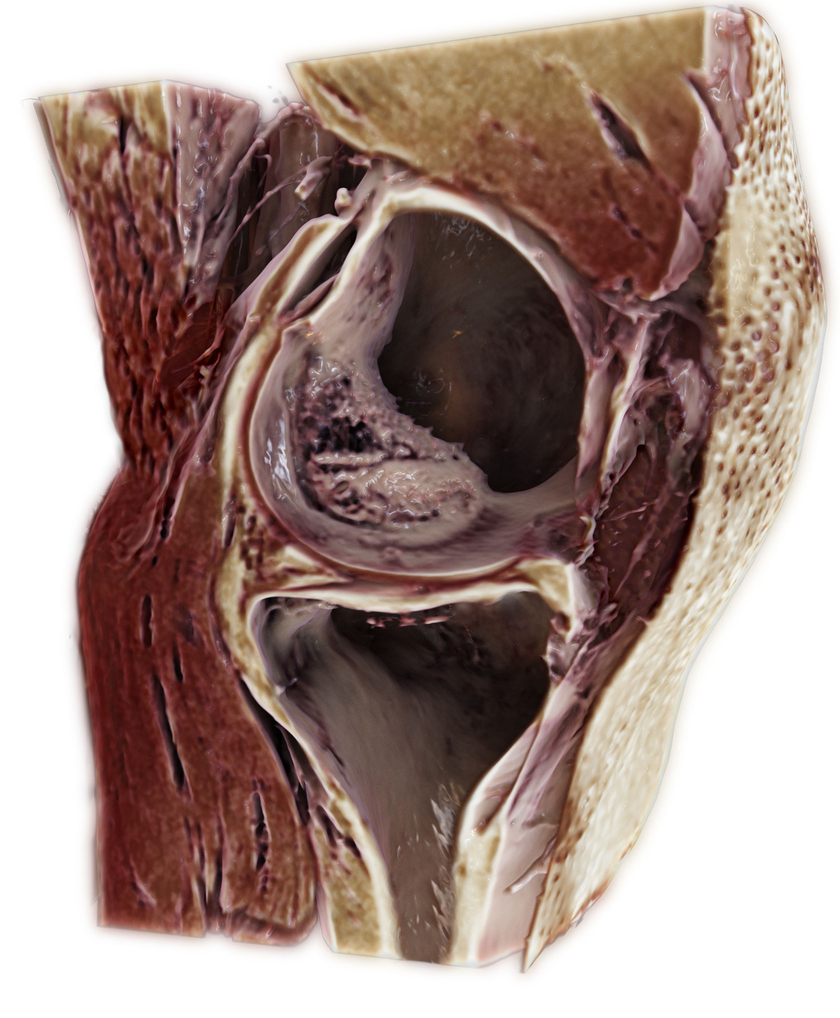

В декабре 2017 года на ежегодной конференции общества рентгенологов Северной Америки (RSNA) Siemens Healthineers представила приложение для МРТ-сканеров GOKnee3D, которое помогает сократить время, необходимое для комплексного диагностического осмотра коленного сустава. Стандартное исследование этого сустава занимает около 20 минут, тогда как применение диагностического приложения может вдвое ускорить этот процесс.

GOKnee3D позволяет получить трехмерные изображения с высоким разрешением, которые можно оценить во всех возможных плоскостях. Как отмечает производитель, осмотр коленного сустава занимает третье место среди всех типов МРТ-исследований (на него приходится 11% всех сканирований), и такое повышение эффективности исследования поможет сократить время осмотра и ожидания пациентов в очереди

Получение объемного изображения стало возможно благодаря протоколу Caipirinha Space, который обеспечивает более высокую скорость сканирования и оптимальную реконструкцию изображения. Разработкой и клиническим обоснованием данной техники компания Siemens Healthineers занималась совместно с Университетом Джона Хопкинса в Балтиморе, США.

| | GOKnee3D обеспечивает всестороннюю оценку внутренних поражений коленного сустава. Полностью автоматизированный протокол Caipirinha Space обеспечивает высококачественную МРТ-визуализацию всего за десять минут. Высокое разрешение изображений помогает визуализировать аномалии с необыкновенной точностью практически в любой плоскости. Ян Фритц (Jan Fritz), доктор медицинских наук, работающий в университета Джона Хопкинса | |

Благодаря специальным катушкам для колена и автоматической адаптации поля зрения с помощью данного приложения можно получить объемное изображение коленного сустава при минимальной вовлеченности персонала. Приложение GOKnee3D доступно для сканеров Siemens Healthineers, систем Magnetom Skyra 3T и Magnetom Aera 1.5T.[1]